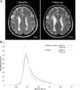

CADASIL or CADASIL syndrome, involving cerebral autosomal dominant arteriopathy with subcortical infarcts and leukoencephalopathy, is the most common form of hereditary stroke disorder, and is thought to be caused by mutations of the Notch 3 gene on chromosome 19. The disease belongs to a family of disorders called the leukodystrophies. [Source: Wikipedia ]